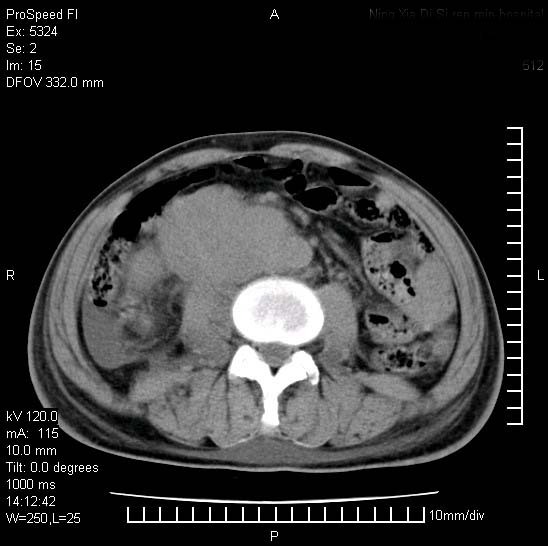

患者阴囊肿大14月,腰痛2个月,咳嗽,咳痰1周,患者现在肾功异常,做增强有些担心,我们用的是欧乃派克.

双肾均有软组织密度舯物,腹膜后淋巴结肿大包饶腔静脉------考虑为恶性占位病变,转移瘤可能。

支持:双肾均见软组织密度肿块影,腹膜后淋巴结肿大包绕腔静脉------考虑为恶性占位病变,转移瘤可能。

腹腔积液,双肾均有稍高密度肿块,主动脉旁广泛淋巴结肿大,融合,无显著肿块坏死征像,多考虑淋巴瘤累及双肾,不排除肾癌伴转移(肾癌这么大应该较多坏死了),另阴囊肿大,不知是实质肿大还是阴囊积液,如是是积液,多为腹腔肿块压近睾丸静脉所致,如是是实性的,多为淋巴瘤

双肾均有软组织肿块伴腹膜后淋巴结肿大融合,右侧结肠旁沟积液;考虑恶性肿瘤。转移瘤?淋巴瘤?

双肾增大,腹膜后多发肿大淋巴结影.首先考虑淋巴瘤.

考虑恶性淋巴瘤侵及双肾,腹膜后淋巴结肿大。